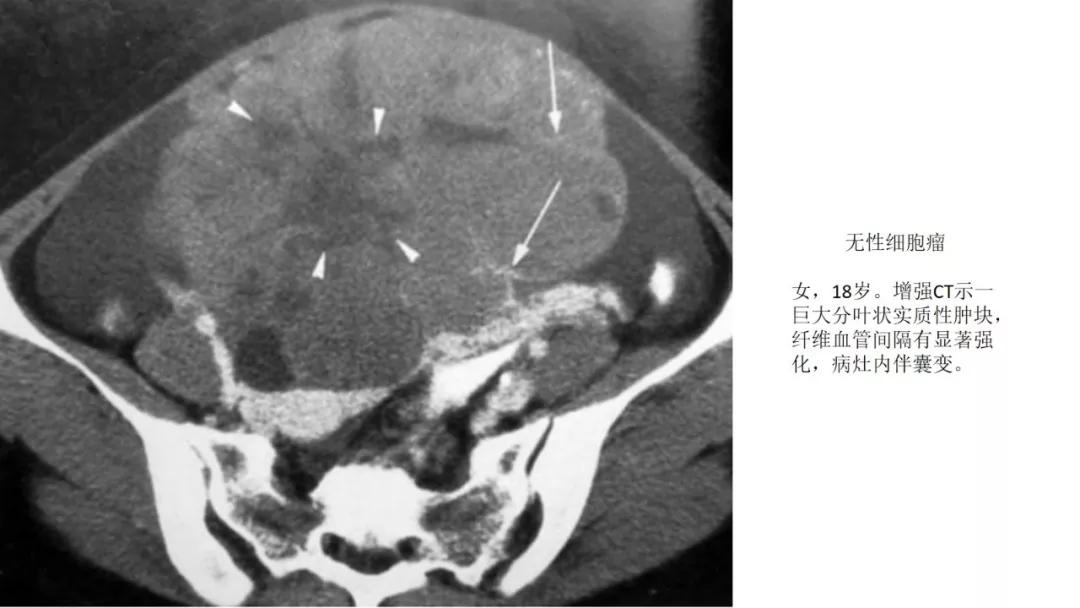

恶性者常呈实性或混杂性肿块,多数边界清楚,可伴有不规则沙粒状钙化。无性细胞瘤常为实性肿块,轻度强化,内胚窦瘤实性成分明显强化,不成熟畸胎瘤呈混杂密度。结合年龄及临床生化检查,有助于诊断。

- 纤维血管分隔呈分叶状:无性细胞瘤